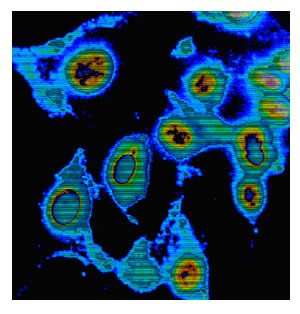

Ukoliko infekcija nastupi preko disajnih organa, onda se pneumonija može smatrati primarnom lezijom, u tom slučaju se ona ne bi mogla smatrati sekundarnom nakon rikecijemije. Ovo je dokazano na eksperimentalnim životinjama od kojih je došlo do plućnih lezija nakon nazalne i trahealne inokulacije rikecija. Karakter pneumoničnog eksudata odgovara etiološki lezijama koje su nađene kod ostalih rikecioza. Kod crvene hepatizacije nađen je u alveolama i bronhiolama jedan fibrinozni eksudat sa limfocitima, velikim monocitima, kasnije i neutrofilima i plazma ćelijama. Kod sive hepatizacije alveolarni zid je odebljan uslijed infiltrata sa makrofagima, Limfocitima i plazma ćelijama. Međutim, nedostaje za rikecioze patognomični vaskulitis i perivaskulitis.

U drugim organima kao što je jetra, slezena, nađeni su milijarni granulomi sa monojedarnim ćelijama. Ovakvi granulomi su nađeni kod biopsije jetre u toku Q-groznice. Coxiella Burneti je otkrivena u makrofagima, plućima, testisu i ćelijama neuroglije. Viđene su sem toga slobodne u tubulima i tutubularnim i epitelijalnim ćelijama. Opisana je patološka slika endokarditisa. Iz ovih lezija je izolirana rikecija.